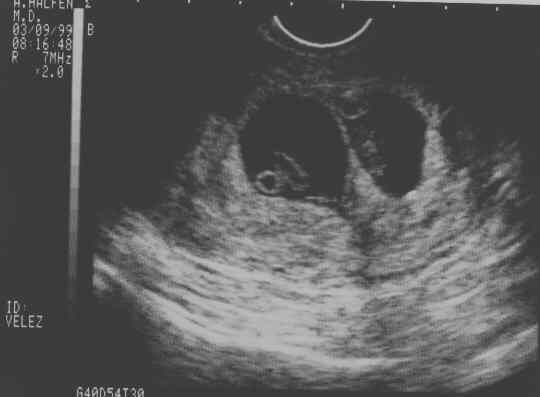

eggs2.JPG - 19.8 K eggs3.JPG - 22.4 K eggs4.JPG - 11.7 K babies-1a.JPG - 21.3 K